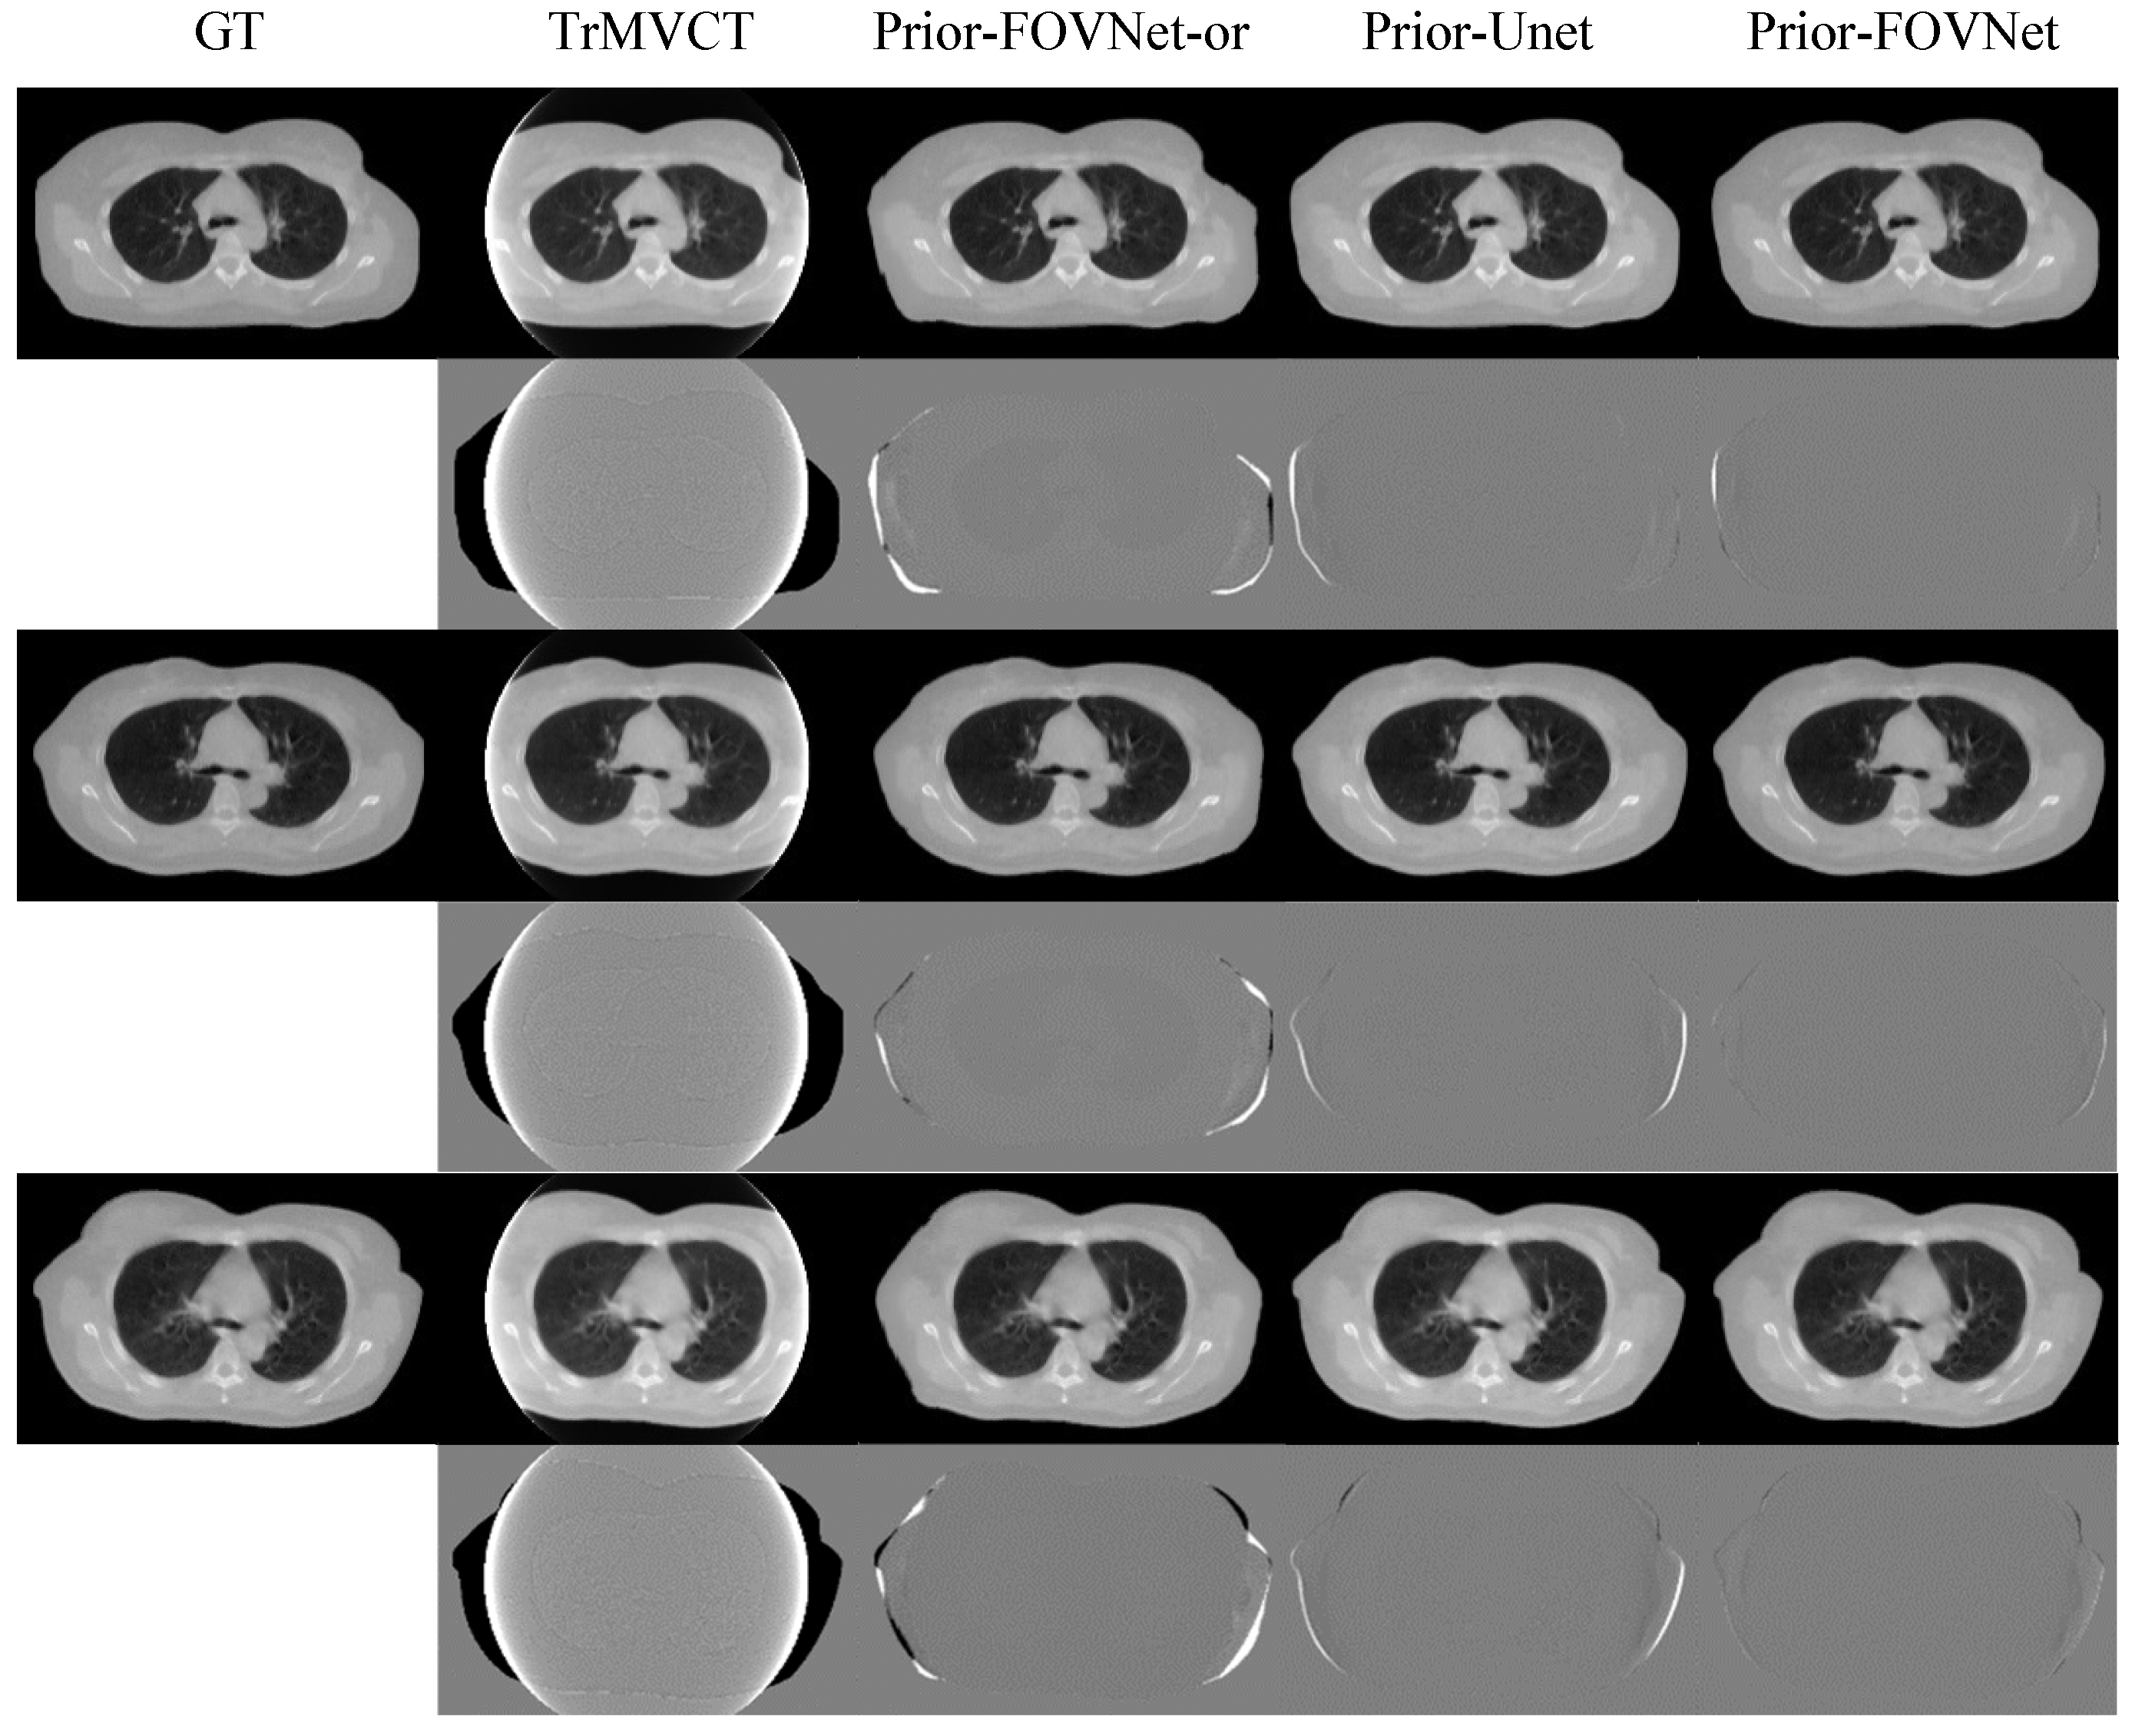

4.3. Results of Clinical Patient Data